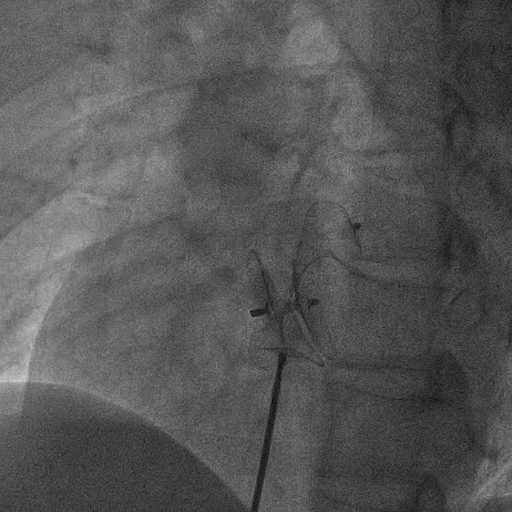

在獲得患者同意后,1月12日,尚福軍主任為患者進(jìn)行了PFO封堵術(shù)。術(shù)中造影可見封堵器殘余漏,尚福軍主任用精湛的技藝,順利通過(guò)封堵器殘余漏裂縫,將右心導(dǎo)管從右房送入左房,且順利到達(dá)肺靜脈;遂行卵圓孔未閉封堵術(shù)后殘余漏再次封堵;且完美釋放PFO封堵器,可見兩封堵器呈“馬蹄蓮”狀,再次術(shù)中造影未見殘余漏。